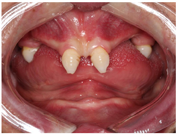

口外检查:颜面部表情自然,意识清楚,无关节弹响压痛,无张口受限,开口4.5cm,最大辅助开口5cm。面部左右不对称,颏点右偏,开口右侧偏斜。口内检查:上颌余留#17,11,21,27,畸形牙;下颌全口牙缺失,牙槽嵴萎缩,角化龈萎缩。唇部肌肉对抗牵拉力量较强,前庭沟浅(图4,图5,图6)。

2周后行游离龈移植手术,在上颌腭侧左右对称各切取1.5mm牙龈组织,包括角化上皮及其下方少许结缔组织。将游离半厚瓣移植到下颌左右侧前庭沟处,缝合创面(图18)。3周后复查,上颌角化龈缺损区域愈合良好,种植体周围角化龈部分恢复,前庭沟加深,种植体周围软组织移动减少(图19)。